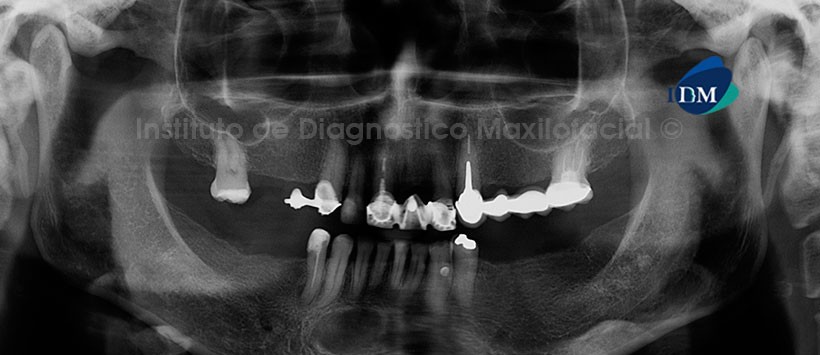

Paciente femenino de 64 años de edad que es referida para la evaluación imagenológica previa al tratamiento odontológico. A la evaluación de la radiografía panorámica se observa la mineralización de los procesos estilohioideos; la neumatización alveolar de los senos maxilares; edentulismo parcial, múltiples restauraciones coronarias y obturaciones de conductos radiculares. Por otro lado, lo que más llama la atención es una imagen radiolúcida unilocular, ovoide, de límites definidos y bordes parcialmente corticalizados; localizada en la región mentoniana de la mandíbula, a nivel de las piezas 41, 42 y 43 (Fig. 1).

La tomografía computarizada de haz cónico, mediante los cortes transaxiales y tangenciales, nos muestra la presencia de una imagen isodensa en la región antes mencionada, la cual no compromete los segmentos radiculares de las piezas vecinas ni tampoco las tablas óseas bucal y lingual. Signos imagenológicos compatibles con una entidad benigna, descartar Quiste Óseo Traumático (Fig. 2 y 3).